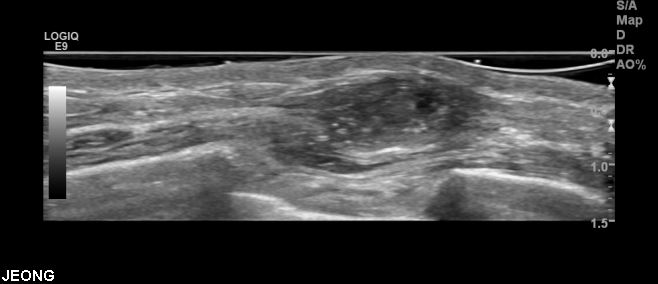

상기환자 70대 여자환자분은 작년부터 만져지는 멍우리 있어 정밀검사위해 내원하신 분으로

본원에서 좌측 2시 방향 조직검사 받으신후 좌측유방 관내제자리암종으로 진단되셨습니다.